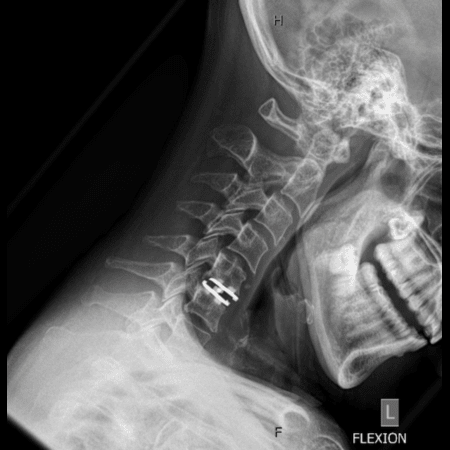

Case Example

MRI of Cervical Spine Disc Herniation

Left-Sided Disc Herniation C6-7 Compressing the Left C7 Nerve Root

• Worsening Neck Pain

• Left-sided Arm Pain

• Left Tricep Weakness

• Anterior Cervical Discectomy & Fusion (ACDF): Removing the damaged disc and fusing the vertebrae.